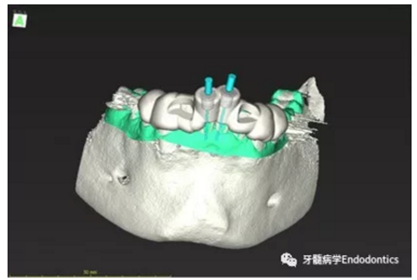

31、41叩痛明顯,牙冠變色(圖1)。溫度和牙髓電活力測試無反應。兩張從不同角度拍攝的x線片顯示,相對于側切牙,雙側下中切牙都有嚴重的根管鈣化(圖2)。41有明顯根尖周暗影,31根尖周暗影不明顯。為進一步證實31是否存在根尖周病變,同時精細觀察31、41的復雜結構,根據歐洲牙髓病學會CBCT應用指南(2014),對患牙拍攝小視野、高分辨率CBCT。CBCT影像證實31、41均伴有根尖周炎和嚴重的根管鈣化(圖3)。距離根尖4mm可見根管影像。 由于患牙根管解剖結構較為復雜,筆者決定使用特殊設計的微型鉆頭(直徑0.85mm)進行“數字化導航牙髓治療”。 因此對下頜進行口內掃描(圖4)。用coDiagnostixTM軟件(Dental Wings Inc.,Montreal,Canada)將CBCT和口內掃描的數據進行處理,該軟件主要用于引導種植。通過該軟件對兩個掃描圖像進行疊加后,虛擬鉆頭尖端沿牙長軸對準根管下段可見部分(圖5)。三維檢查虛擬鉆的正確位置。

內置的軟件工具可以設計鉆針導板(圖6)。該導板可以一個表面鑲嵌語言(stl-)文件導出,并用3D打印機(Objet Eden 260 V, Material: MED610, Stratasys Ltd.,Minneapolis, MN, USA)制作。

圖4.下頜牙口內表面掃描的表面鑲嵌語言(stl-)數據。

圖5.虛擬設計的微創(chuàng)根管入路。虛擬鉆針的尖端能到達鈣化根管X線影像中的可見部分。

圖6.設計導板。